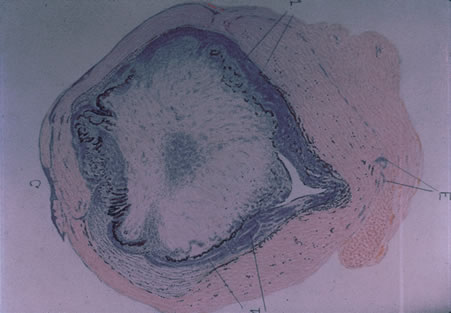

Reactivation of HSV may be precipitated by fever, trauma, menstruation, emotional stress, or systemic illness. Recurrent episodes of HSV type 1 and type 2 are generally preceded by several hours of burning, itching, and tingling before the skin vesicles appear. Systemic symptoms tend to be mild or absent, with the exception of recurrent adenopathy. The lesions appear similar to the primary infection and are frequently painful. The most frequent regional recurrences of HSV type 1 are on the vermilion border of the outer lip (herpes labialis) and in the eye (Fig. 2). Recurrences of HSV type 2 characteristically produce lesions on the penile shaft and glans in the male and on the labia and perineum in the female. Headache and aseptic meningitis are occasionally associated with a genital recurrence. Further recurrences may be seen at monthly or yearly intervals.

In primary ocular HSV infections, a severe follicular conjunctivitis with regional adenopathy is present. Vesicles may appear on the eyelid skin or lid margin, producing blepharitis (Fig. 3). Corneal involvement initially takes the form of a superficial punctate keratitis, which may progress to dendritic or geographic ulceration. Stromal infiltrates and uveitis are less common and relatively mild in primary disease. In uncomplicated cases, lesions usually heal completely in 2 to 3 weeks without scarring. Most cases of ocular HSV are recurrences. Recrudescent ocular herpes may take the form of dendritic or geographic ulcers, recurrent erosions, interstitial or disciform stromal keratitis, and anterior uveitis.3 HSV may also be an agent of retinitis and acute retinal necrosis (Fig. 4).